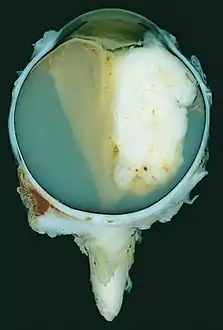

| A pathology specimen of a retinoblastoma tumor from an enucleated eye of a 3-year-old female | |

Morphology

Gross and microscopic appearances of retinoblastoma are identical in both hereditary and sporadic types. Macroscopically, viable tumor cells are found near blood vessels, while zones of necrosis are found in relatively avascular areas. Microscopically, both undifferentiated and differentiated elements may be present. Undifferentiated elements appear as collections of small, round cells with hyperchromatic nuclei; differentiated elements include Flexner-Wintersteiner rosettes, Homer Wright rosettes,[29] and fleurettes from photoreceptor differentiation.[30]